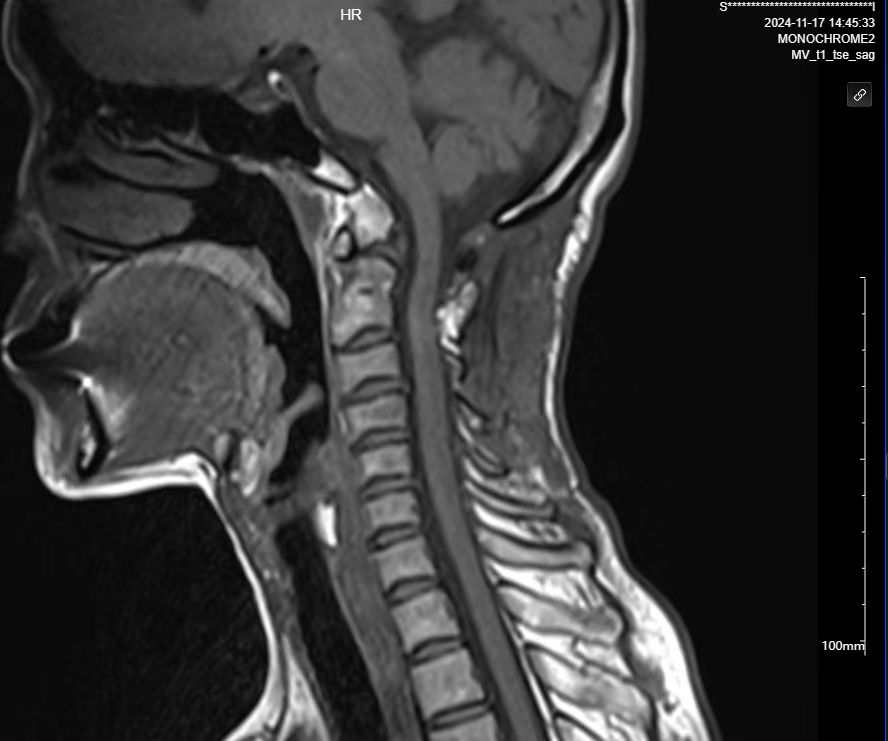

二次手术#

• 日期:2024.06.14

• 医院:北三医院

• 主刀:王超

• 术后状况:手脚无力的症状消失,低头时间久了脖子手术的地方酸痛。

• 术后影像:

• 2024.11.07,复查,对位良好。